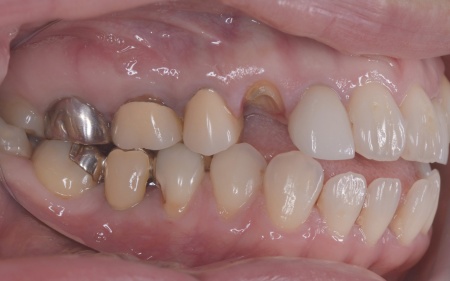

40代女性 矯正治療で噛み合わせを整えたあとセラミックの被せ物・詰め物で修復した症例

「左下の奥歯が欠けたのと、右上の差し歯が取れた」とご相談いただきました。

拝見したところ、左下と右上の歯はともに大きな虫歯があり、歯だけでなく被せ物を支える土台の部分にも影響が及んでいました。

さらに、ほかの歯に入っている詰め物や被せ物の周囲にも、過去に治療した部分に再び虫歯ができる二次カリエスが複数見つかりました。

また、噛み合わせを確認したところ、奥歯で噛み合わせた際に上下の前歯が当たらず隙間ができる開咬(かいこう)が認められました。

実際に患者様の場合も、特定の歯に長期間強い力がかかり続けたことで歯や修復物の破損、さらには口腔内全体のトラブルにつながった可能性が高いと考えられました。